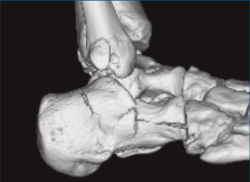

Se trata de un varón de 19 años que ingresa en reanimación tras precipitarse desde una altura de aproximadamente 10 metros. El paciente presenta una fractura estallido de L3 con afectación del canal medular junto con una fractura del vértice inferior de L4, así como una fractura luxación de calcáneo, asociada a una fractura del maléolo peroneo y del maléolo tibial posterior (Figuras 1 a 6) diagnosticadas mediante TC total body (por eso no se dispone de radiografías simples al momento del ingreso). Como podemos comprobar, se trata de una fractura de doble trazo de tipo hundimiento/depresión de la carilla articular (Figuras 5 y 6).

Figura 5. Fractura maléolo peroneo, luxación astrágalo, fractura de doble trazo en calcáneo.

Figura 6. Fractura de doble trazo; se evidencia afectación de la articulación calcaneocuboidea.